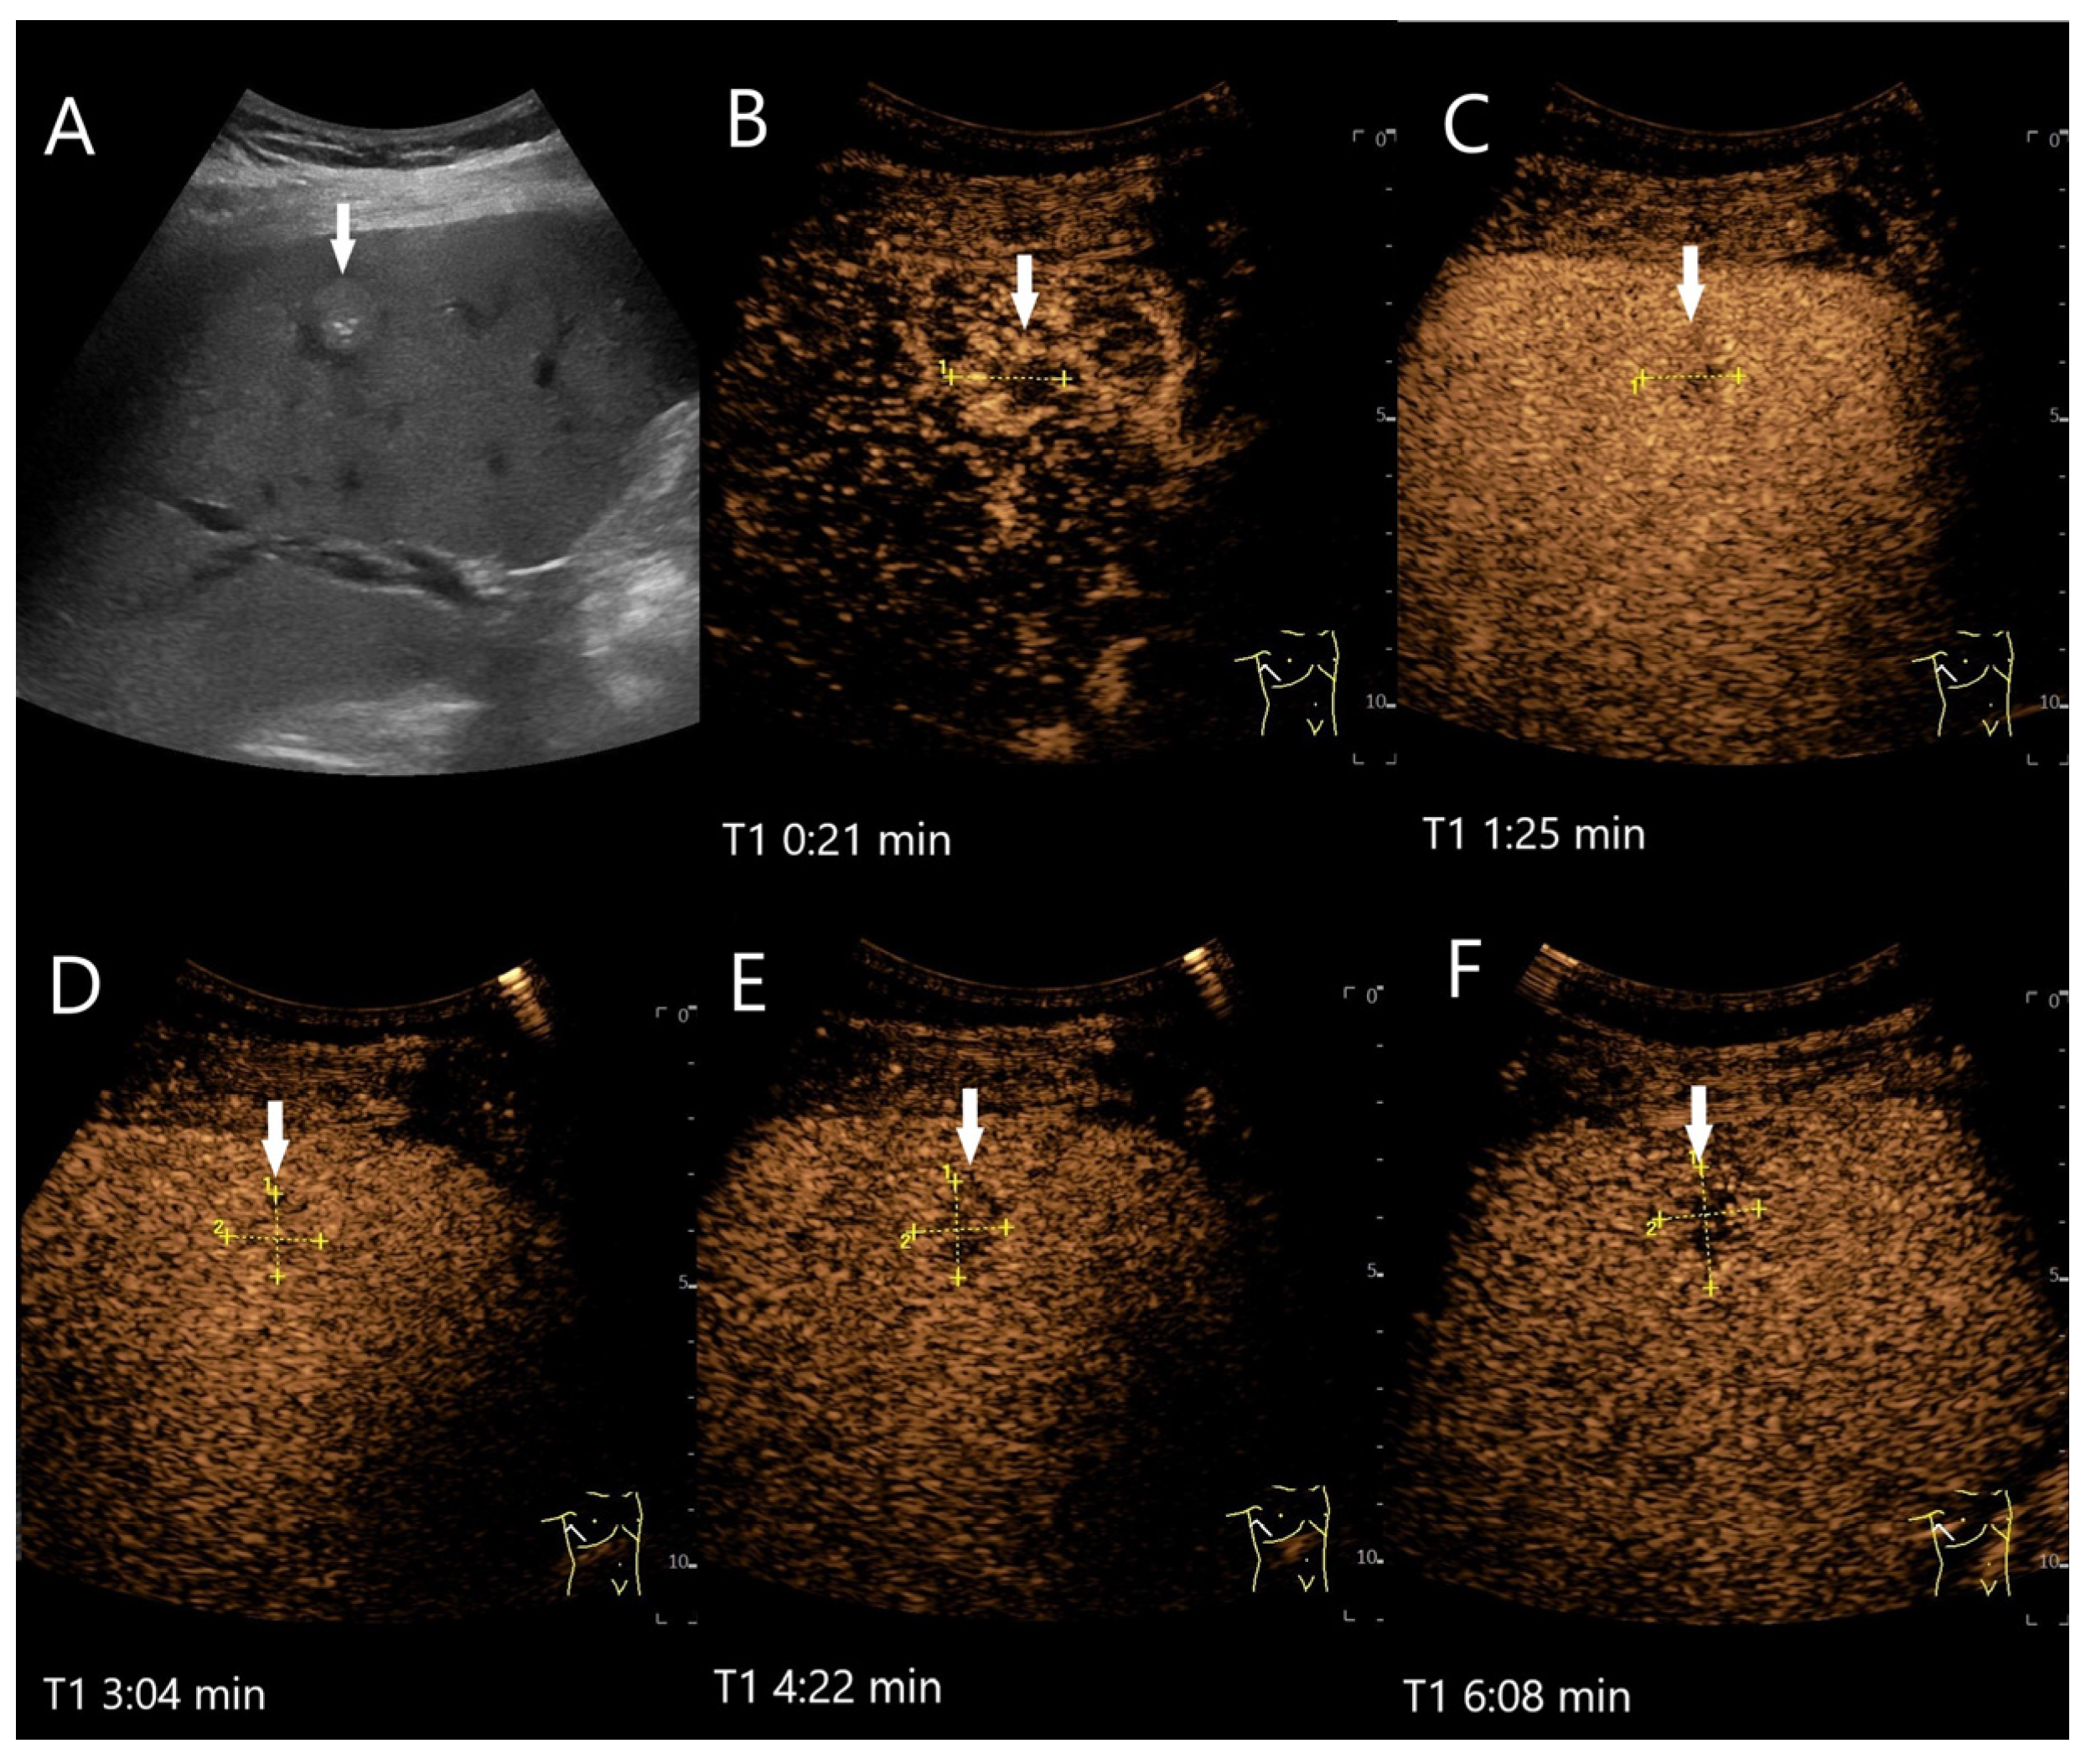

Figure 2.

Partially fibrosed hemangioma. As part of a staging examination for adenocarcinoma of the gastro-esophageal junction, a 19 mm, smoothly bordered hyperechoic lesion (arrow) with an implied hypoechoic rim and punctate echogenic reflexes is diagnosed in the liver (A). On CEUS, the small lesion (between the markings) shows a marginal contrast image that is not completely smooth (B). In the PVP after 1:25 min, most of the lesion is enhanced, but slightly less than the surrounding parenchyma and with a small portion that is clearly hypoenhanced (C). After 3:04 min, the lesion is slightly hypoenhanced (D), while after 4:22 min (E) and 6:08 min (F), the lesion shows an unequivocal hypoenhancement. The lesion did not clearly correspond to a hemangioma on computed tomography either. This was the reason for a US-guided biopsy. Histology revealed a hemangioma, partially fibrosed and with tiny calcifications.

Various causes are discussed for washout in hemangiomas with hypoenhancement in the LP. The first one is caused by a technical aspect: UCA bubbles can be destroyed by too intense and prolonged exposure to ultrasound waves. If the ultrasound power (characterized by the Mechanical Index, MI) has been set too high, this further contributes to UCA bubble destruction. If hemangiomas fill up more slowly than in the surrounding liver parenchyma, the degree of disruption may be greater than the replenishment. It is, therefore, recommended that the ultrasound examination is not carried out continuously up to the 5th minute, but intermittently [16]. If an FLL possibly represents a hemangioma, we prefer a video loop in the AP and then every 30 or 60 s in the PVP and LP. However, in our experience, there are hemangiomas that still show a washout even with this procedure. A mild fade in the PVP and hypoenhancement in LP are described for hemangiomas with rapid onset [27]. In hemangiomas with rapid filling, it is debated whether the rapid filling has an equally rapid outflow, which in turn is more pronounced than the contrasting of the surrounding liver parenchyma [4]. Finally, fibrosis or scars lead to hypoenhancement during all contrast phases. Fibrosis in any type of lesion reduces the sinusoidal network, and thus, the vascular volume [4]. Hemangioma with a faint washout, in which fibrotic lesions have been described histologically, is demonstrated in Figure 2. A pronounced hypoenhancement in the LP of a hemangioma is shown in Figure 3.